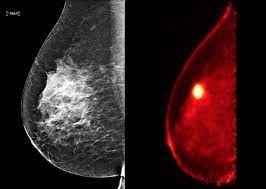

Can Chest Ct Scan Detect Breast Cancer : Metastatic Breast Cancer In The Lungs Symptoms And Diagnosis - When a breast cancer has been diagnosed, some people have a ct scan of their chest and tummy (abdomen) to stage the breast cancer.. The value of preoperative staging chest computed tomography to detect asymptomatic lung and liver metastasis in patients with primary breast carcinoma. Ct scans can help doctors: Right now, ct scans are not used routinely to evaluate the breast. Computed tomography scan, ct scan, cat scan, and spiral or helical ct a ct scan can help doctors find cancer and show things like a tumor's shape and size. Areas commonly scanned for cancer include the head, neck, chest, abdomen, pelvis, or limbs.

By comparing ct scans done over time, doctors can see how a tumor is responding to treatment or find out if the cancer has come back after treatment. Staging tells the doctor how big a cancer is and whether it has spread. Right now, ct scans are not used routinely to evaluate the breast. Conversely, a mammogram or ultrasound can detect breast and prostate tumors, but it could completely miss a bone tumor. Several types of cancer can form in the breast, making it the second most common cancer that affects american women.

It is sometimes called computerized tomography or computerized axial tomography (cat). I was told that a bone scan is often used for diagnosis whereas ct scans can be used for follow up scans. This test is done because it is common for breast cancer to metastasize to the lungs. Study the brain, spine, chest, abdomen or pelvis find out the size, shape and location of tumours How do ct scans work? When the doctor knows this, they can choose the best course of treatment and maybe even predict your chances of recovery. Metastatic patterns and their prognosis. A trained radiologist will interpret the ct scan images and send the detailed results. If you have a large breast cancer, your doctor may order a ct scan to assess whether or not the cancer has moved into the chest wall. Do ct scans detect breast cancer? Right now, ct scans aren't routinely used to look for breast cancer, but may be used to look at chest, spine, or abdominal problems, such as a herniated disc or lung disease. Benefits of a ct scan. Cas article google scholar 6.

What Tests Will My Doctor Use To Make A Cancer Diagnosis Everyday Health from images.everydayhealth.com My question is, would these tests show breast cancer, and secondly, would it be risky to have a mammogram so soon after these tests that use radiation. Sandy,i asked my onc.he says ct's can pick up breast cancer depending part on location.i guess it's like real estate,location,location,location,lol.but seriously theradiologist who read my lung ct in november wrote in his report specifically there was no evidence of breast cancer.i guess due to them watching a lymph gland for 2 years on my rt breast.it was fine in mammogram in october so i am now back to yearly,thank god,andib This test is most often used to look at the chest and/or belly (abdomen) to see if breast cancer has spread to other organs. Other names for this test: Breast cancer affects over 200,000 women each year. So far, researchers at the university have. The value of preoperative staging chest computed tomography to detect asymptomatic lung and liver metastasis in patients with primary breast carcinoma. Ct scans can help doctors: